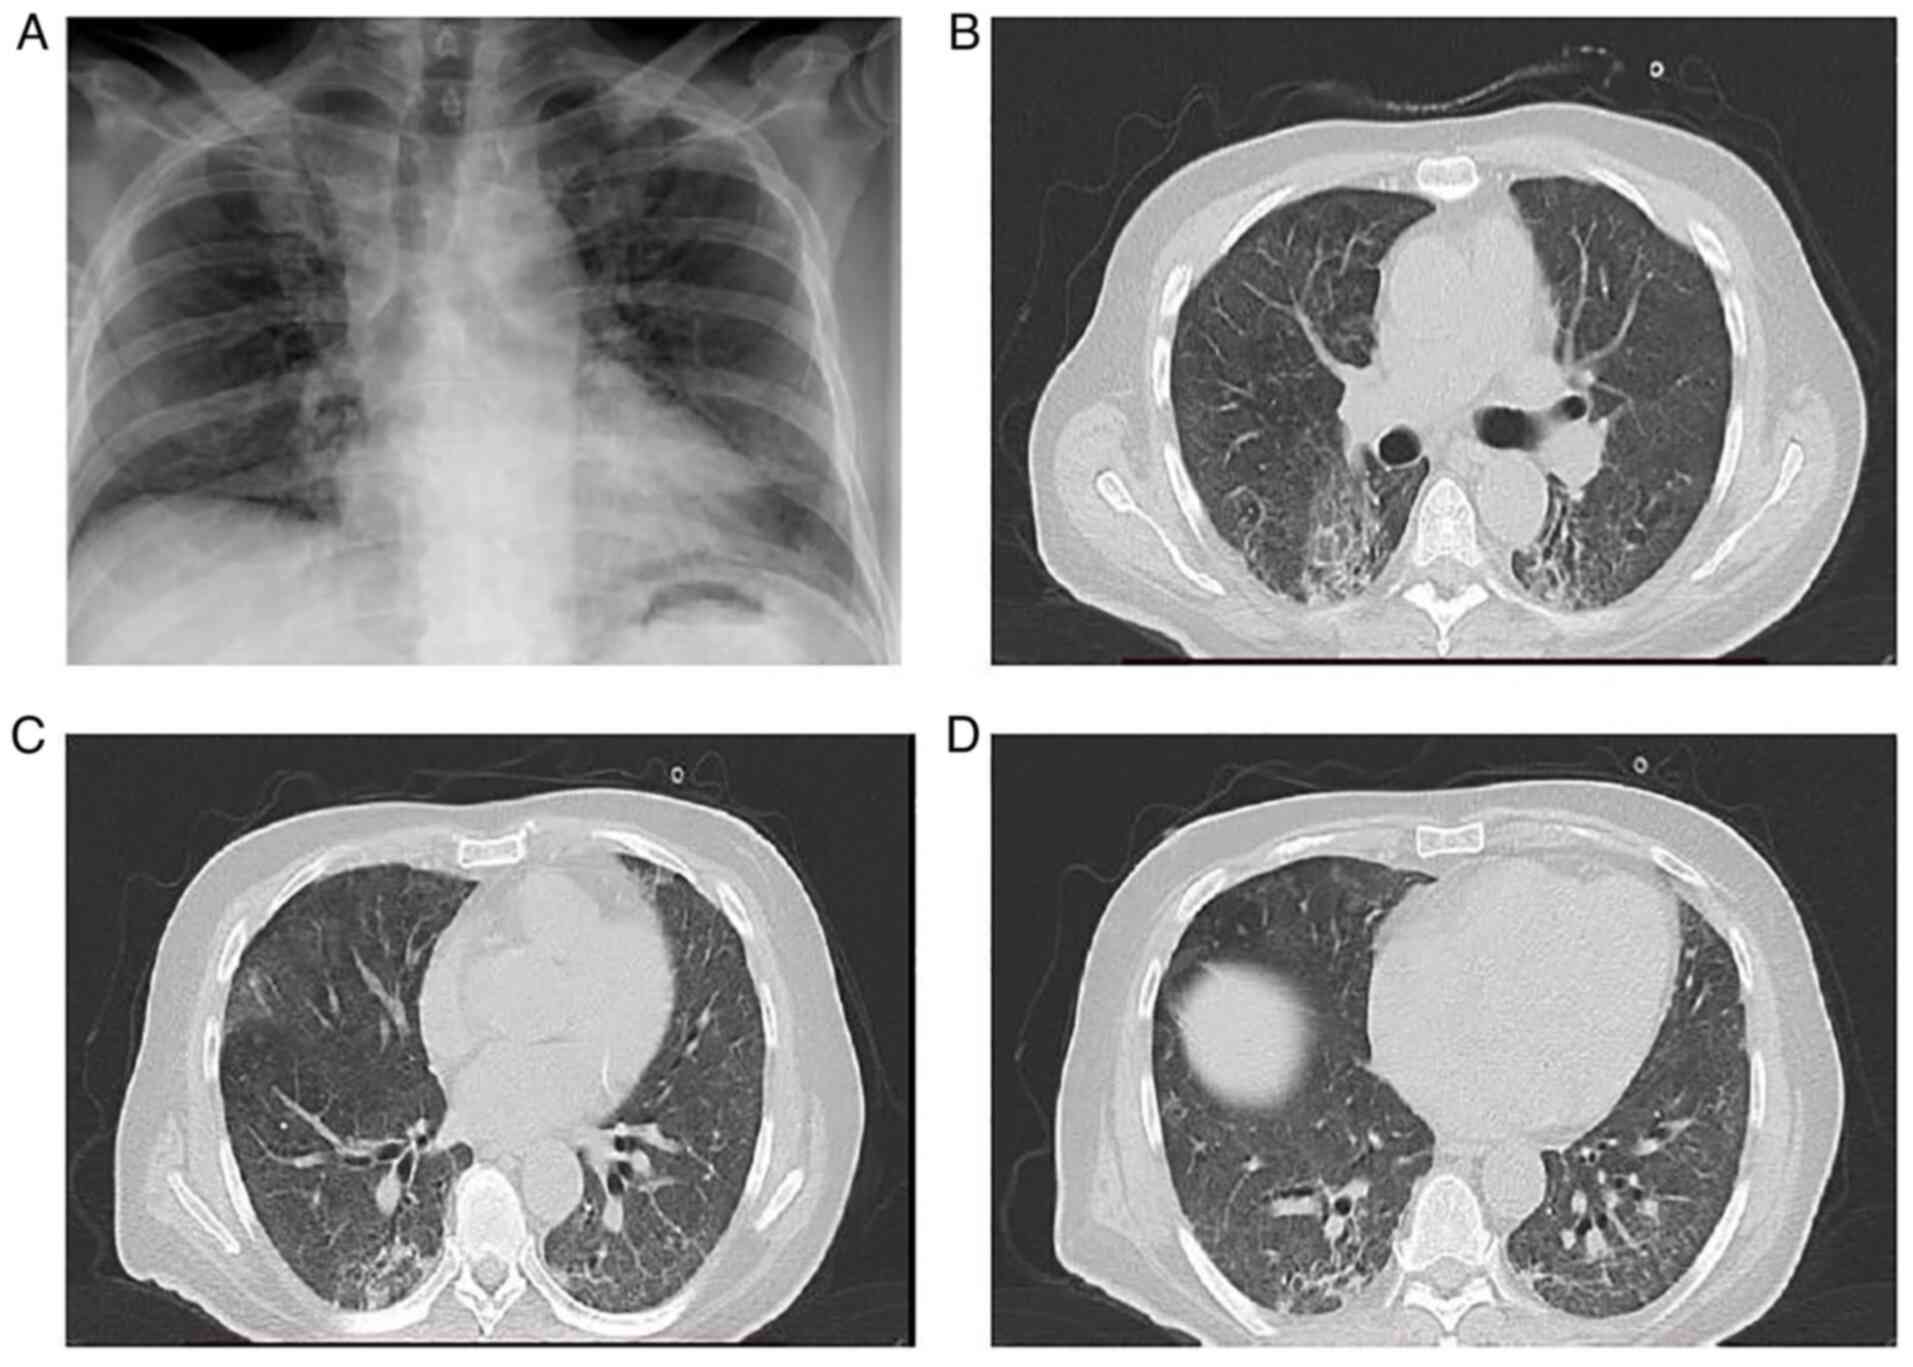

The patient underwent a new chest X-ray which revealed worsening infiltrates in all lung fields (Fig. 2A). He also underwent a chest CT scan and chest computed pulmonary angiogram (CTPA), which revealed bilateral peripheral GGO infiltrates and consolidation in both lower lung lobes, with areas of reversed halo sign (Fig. 2B-D). There were no findings suggesting pulmonary embolism. Simultaneously with this radiological and respiratory deterioration, the patient presented with recurrent fever and significantly elevated CRP levels (279.31 mg/l; reference range, 0-5 mg/l). He received antimicrobial therapy with intravenous piperacillin-tazobactam at 4.5 g four times daily and intravenous linezolid 600 mg twice daily. Blood and sputum culture did not reveal any infectious microorganisms. In addition, serum procalcitonin levels were within the normal range. The patient did not exhibit any improvement with antibiotics. Based on clinical and radiological data, COVID-19-associated OP was suspected, and systemic corticosteroid therapy (methylprednisolone 1 mg/kg/day) was initiated. On day 23 of hospitalization (day 30 of illness), 3 days following the commencement of corticosteroid therapy, his oxygenation level markedly improved. A chest X-ray and CT imaging performed on day 14 following the commencement of corticosteroid therapy (day 34 of illness) revealed an improvement of lung infiltrates (Fig. 3). The levels of CRP also returned to normal. The methylprednisolone administration was decreased to 40 mg, and the patient was discharged on day 39 following admission (day 46 of illness). Following discharge, the methylprednisolone administration was decreased to 32 mg for 10 days, 16 mg for 10 days and 8 mg for 10 days, and discontinued thereafter. The patient did not present with a relapse on a follow-up at 3 months after discharge.

Figure 2

Chest X-ray and computed tomography of the patient in case 1 on day 14 of hospitalization. (A) Chest X-ray illustrating lung infiltrates in all lung fields. (B) Chest computed tomography illustrating bilateral peripheral ground glass infiltrates in upper lung lobes. (C and D) Chest computed tomography illustrating consolidation in both lower lung lobes, with areas of reverse halo sign.

Figure 3

Chest X-ray and computed tomography of the patient in case 1 performed on day 14 following the commencement of corticosteroid therapy. (A) Chest X-ray illustrating an improvement in lung infiltrates in all lung fields. (B) Chest computed tomography reveals improvement in bilateral peripheral ground glass infiltrates in upper lung lobes. (C and D) Chest computed tomography reveals improvement in lung lesions compared to Fig. 2C and D.